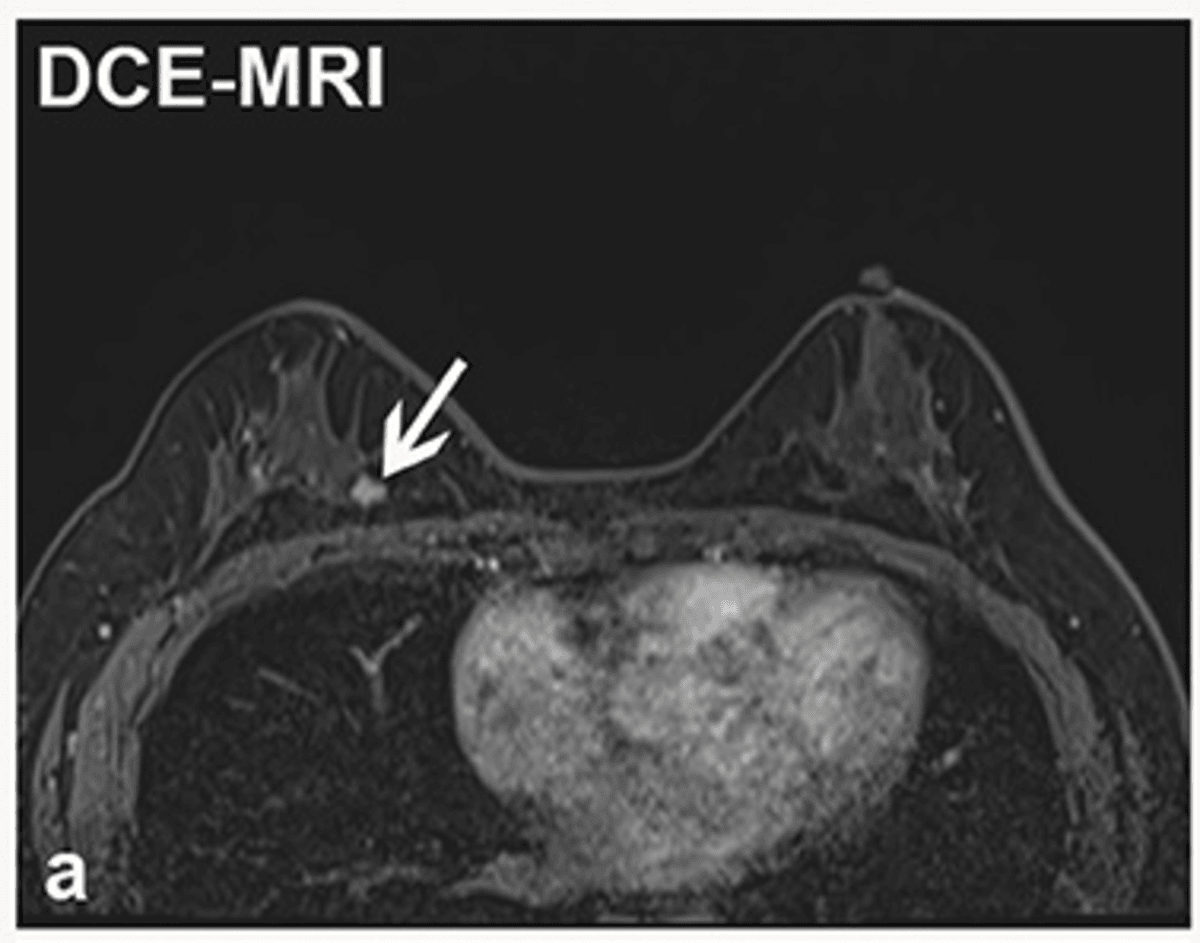

The earliest stages of breast cancer may not cause any symptoms, emphasising the importance of imaging (such as mammograms or MRIs) for the earliest detection of breast cancer.

High-risk individuals, such as those with a family history of breast cancer or with dense breasts, could benefit from MRI screening as opposed to standard mammograms10.